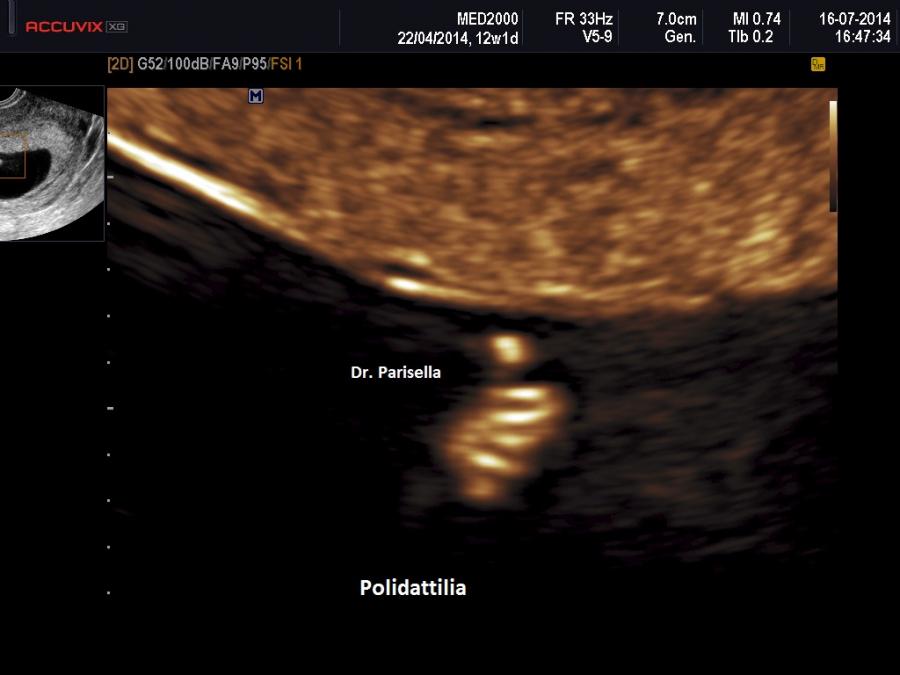

Meno frequentemente è presente polidattilia postassiale; se e’ presente coinvolge mani e piedi.